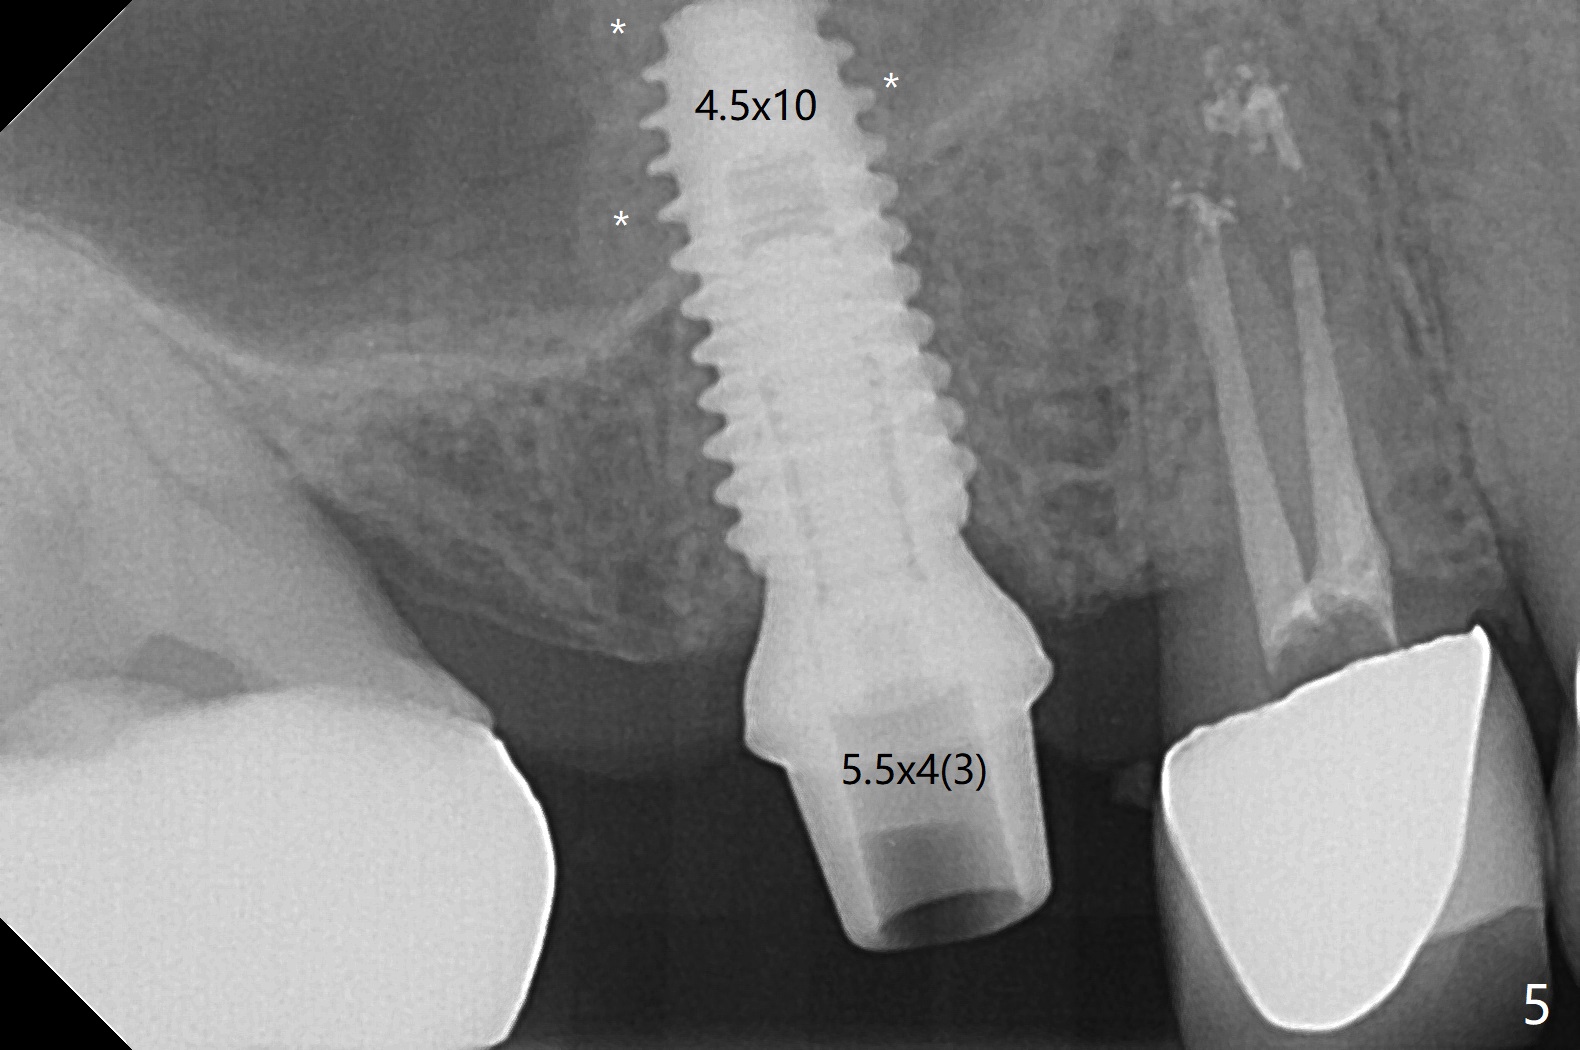

After flattening the root stump with surgical burs and bone trimmer at #4 (Fig.1), it is difficult to use point drill and 2.2x7.3 mm drill because of incomplete engagement of drill cylinder with guide sleeve (Fig.2). The initial osteotomy seems to be buccal. With removal of the remaining root, it is much easier to finish osteotomy (better engagement of drill cylinder with the sleeve) and sinus lift with dummy implants (Fig.3,4 (*: bone graft)). Finally a 4.5x10 mm implant is placed (basically in the middle of the socket with even buccal and palatal gaps) with primary stability and a cemented abutment is hand tightened (after 5.5 mm profile drill) for an immediate provisional (Fig.5). The gingiva is healthy around the provisional with almost perfect seal 2 weeks postop (Fig.6 P). There is no obvious bone loss 7 months postop (Fig.7). There is apparent mature bone in the sinus 9 months postop (Fig.8 *).